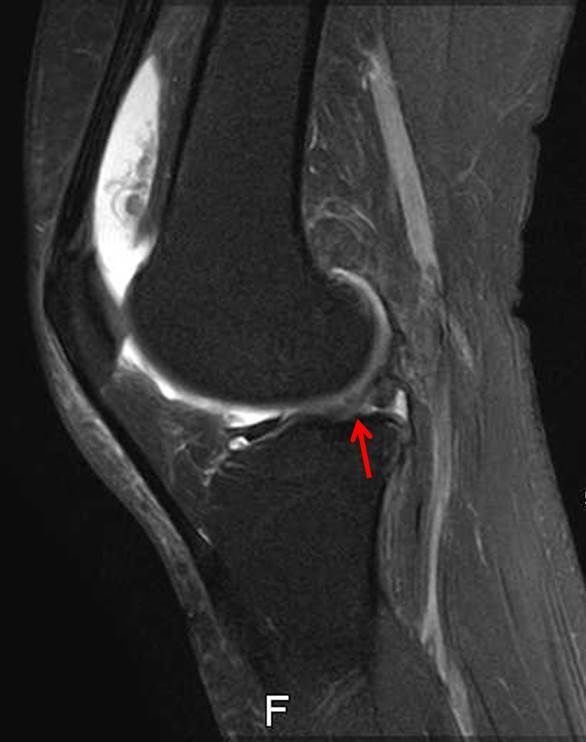

画像所見

| レントゲン | MRI | |

| 骨傷なし、骨棘あり Kellgren-Lawrence分類gradeⅡ | 外側半月板のフラップ損傷あり 骨損傷あり | |